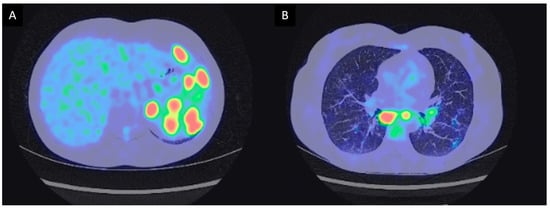

3.2.1. Case Description

| 3 | M | 45 | Maghrebian | Altered general condition with 2 kg weight loss. Hard, fixed and painless left sus clavicular and cervical adenopathies. Sino nasal obstruction with retropharyngeal adenopathies with cavum mucosal thickening | Atypical lymphadenopathies, exclusive extrathoracic multi organ involvement. | 24 months | Hodgkin’s lymphoma | Chemotherapy (ABVD, ICE) | Currently continuing chemotherapy |

| 4 | F | 56 | Caucasian | Cervical and axilar lymph nodes. Cavum tumefaction. Granulomas without atypical features. Atypical CD30+ cells on repeated lymph nodes sampling. | Cavum infiltration and exclusive extrathoracic lymph nodes. | 72 months | Biclonal lymphoma (Hodgkin and Diffuse large B cell lymphoma). Hodgkin disease was already present at disease onset 6 years before (second-look histological examination). | Chemotherapy (R-CHOP 8x) | Healing |

| 5 | M | 54 | Maghrebian | Lower esophagus stenosis with peri esophageal adenopathies and dysphagia. Paratracheal and subcarinal and antero superior mediastinal lymph nodes. Histological examination concordant with Piringer Kuchinka’s lymphadenitis. | Compressive phenomenon. No hilar lymph nodes with anterior mediastinal lymph nodes. | 40 months | EBV positive Hodgkin’s lymphoma | ABVD 6 courses | Healing |